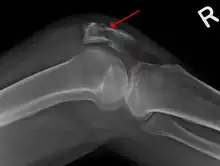

A fracture of the patella seen on a lateral view